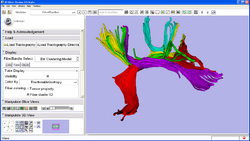

Centerline extraction using Voronoi diagrams (Luca Antiga, Daniel Haehn)